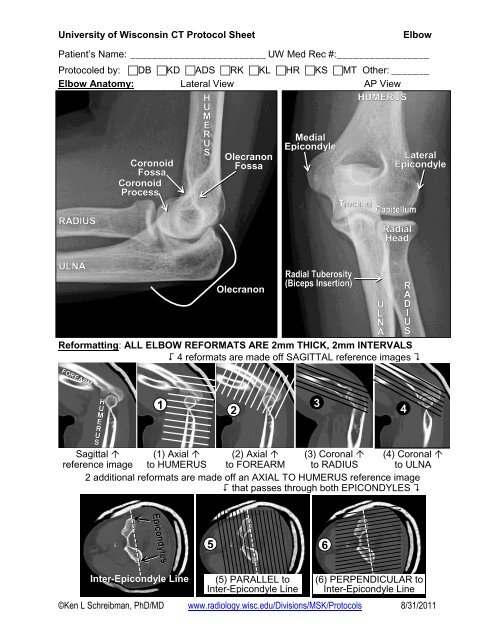

11+ Anatomy Elbow Radiology PNG

11+ Anatomy Elbow Radiology PNG. At the emergency assistance department, it is used primarily to demonstrate/exclude a fracture. I am a radiology physician from california, usa.